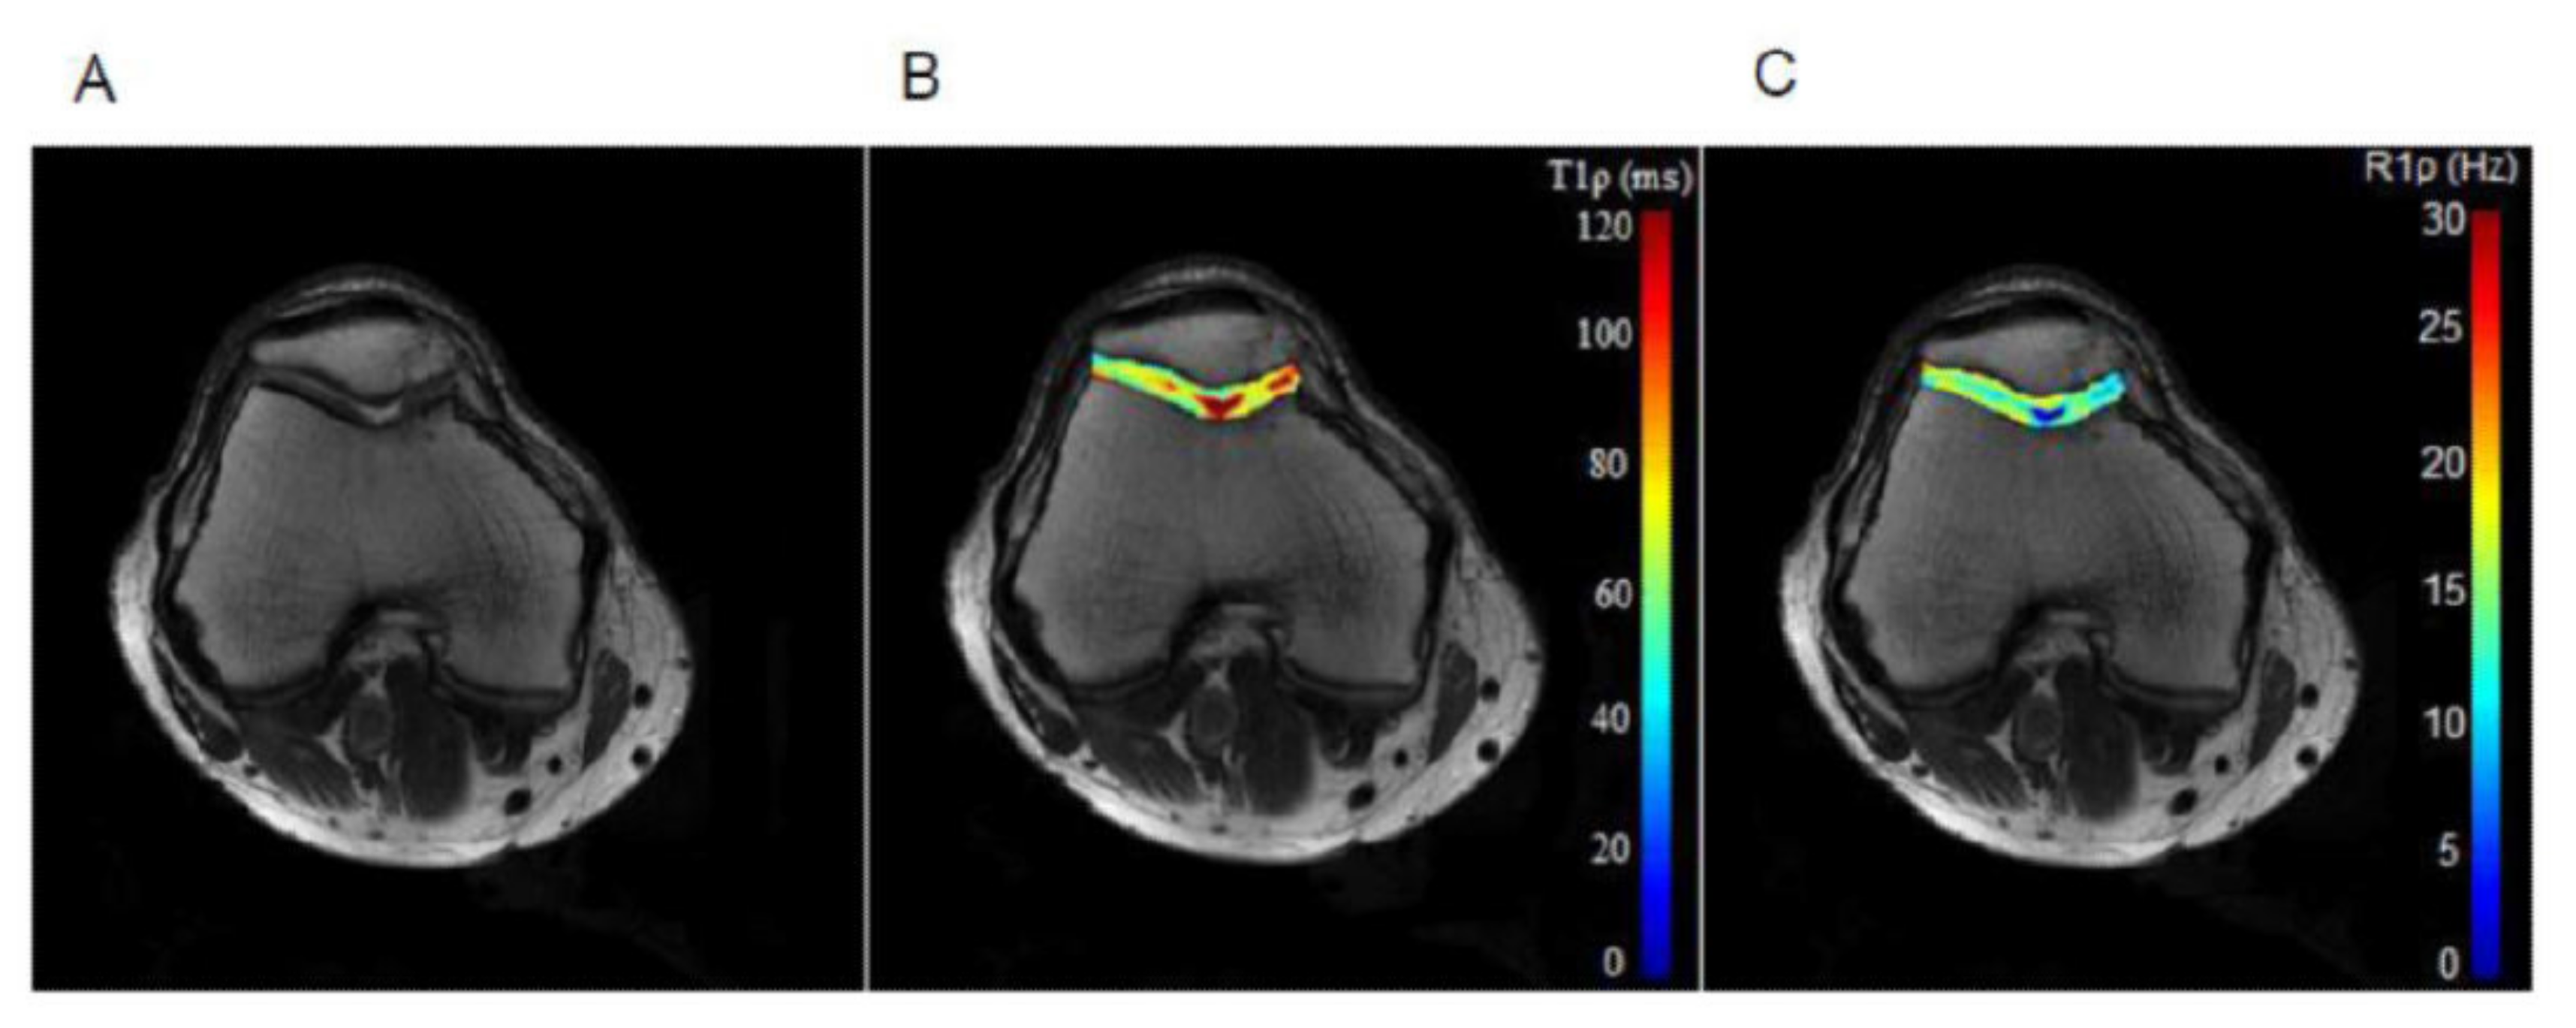

T1๐บ relaxation is typically modeled and fitted using a monoexponential, Eq. 1, similar to T2 relaxation, and a linear least squares fitting algorithm can be used. However, depending on the sequence, the signal model may need additional complexity to account for the effect of T2๐บ relaxation, as in Eq. 2 (Charagundla et al. 2003). An example T1๐บ relaxation map of cartilage in the knee is shown in Figure 3. The model used could also account for chemical exchange (Chopra et al. 1984) and Cobb et al (Cobb et al. 2014).

Figure 3. An example T1๐บ relaxation map of cartilage in the knee, using a spin-lock frequency of 350 Hz, five TSLs linearly spaced from 2-82 ms, and TR/TE 3300 ms/10 ms. Reproduced with permission from (Wang et al. 2015).